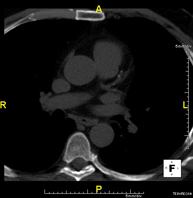

- Chest CT

Diagnostic test that provides high definition anatomical images of the chest (lungs, heart, mediastinum, great vessels, rib cage, etc.) using CT (Computed Tomography) equipment. These images are then examined on a workstation that allows bidimensional reconstructions in different planes of space and also 3D reconstructions (volumetric). Some studies require the use of an iodinated contrast agent to improve image definition.

- Thoracic aorta CT angiography

Diagnostic test to examine the thoracic aorta (main artery of the thorax) using CT (Computed Tomography) equipment. This technique requires the use of an iodinated contrast agent, and provides high definition anatomical images. The use of MDCT (Multidetector Computed Tomography) shortens scanning time, reduces radiation dose and improves image quality. The multiple detectors used in certain studies enable imaging to be synchronised with the heartbeat, a technique used to study the aortic valve and aortic root (the first few centimetres), where the heartbeat often distorts images due to movement.